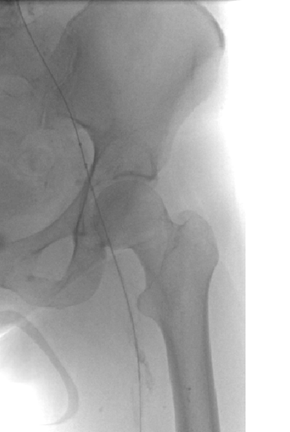

Venograma en posición de decúbito prono de la rama ilíaca izquierda que indica una estenosis causada por el tumor que comprime la uretra y la vena ilíaca externa izquierda.

Eliminación razonable del trombo en las venas ilíacas tras una sola pasada del catéter DVX de AngioJet (25 mg de tPA en 250 cc de solución salina normal).

Venograma final tras la aspiración con catéter grande y tratamiento de la estenosis subyacente (debido a la compresión extrínseca del tumor) con un stent de 16 mm con el balón inflado a 12 mm.

Tiempo total: <90 minutos. Flujo interno perfecto de la parte posterior de la rodilla a la vena cava inferior (VCI).